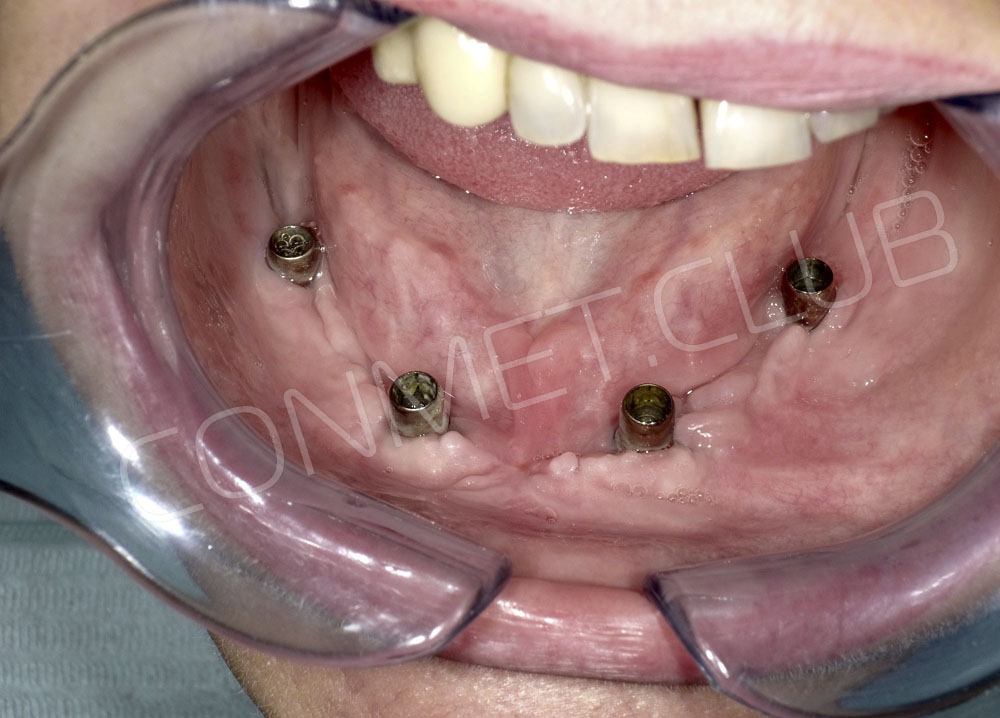

Сама же операция длиться 20-50 минут в зависимости от количества утраченных зубов. В процессе этой операции, после проведенной местной анестезии, делается разрез на слизистой, она приподнимается и субпериостальный имплантат укладывается на кость. После этого рана фиксируется несколькими швами и все! Через 10-14 дней мягкие ткани срастаются и надкостница надежно удерживает имплантат на месте. Нет необходимости ждать несколько месяцев, как это бывает в случае с внутрикостными винтовыми имплантатами.

Новые, искусственные зубы фиксируются к этому имплантату стандартными, трансокклюзионными винтами на 1-14 день (в данном клиническом случае на 5 сутки) и по существу являются несъемными!

И в-четвертых: небольшой фрагмент из операции по восстановлению всех утраченных зубов на верхней челюсти. По сути эта операция полностью повторяет протокол и этапность операции представленной в первой части статьи, за исключением того, что искусственные зубы были зафиксированы сразу после операции. Со слов самой пациентки, процесс жевания был совершенно безболезненным с самого первого дня.